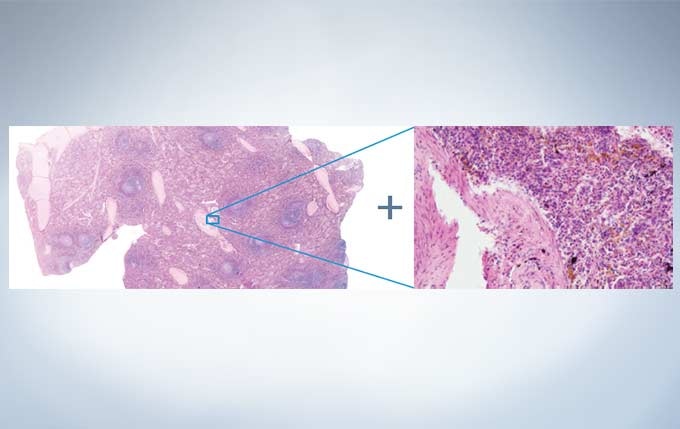

Easily know the location of interest with the Position Navigator

The position navigator adds convenience to the operator’s workflow because it creates a map to help users keep track of their location within the specimen; this is especially useful when making observations at high magnification. This is achieved without the need for a motorized or encoded stage. The low-magnification map of the sample containing all of the pertinent location information can be stored along with the high-magnification observation image, making it convenient for record keeping or creating presentation materials. *The accuracy of the map creation and the position navigation depends on observed samples...

Context Map And High-Magnification Images Stored in a Single File

The metadata images used in the camera’s mapping feature can also be used as stand-alone images. In addition, the entire overview map and high-magnification image can be saved and exported in a common file format for enhanced flexibility. Users are able to place markers in real-time on the overview map to highlight potential areas of interest, making it easy to go back and re-image previously viewed areas.